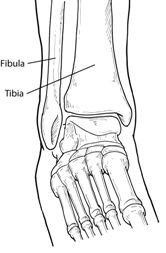

A fracture is a partial or complete break in a bone. Fractures in the ankle can range from the less serious avulsion injuries (small pieces of bone that have been pulled off) to severe shattering-type breaks of the tibia, fibula, or both.